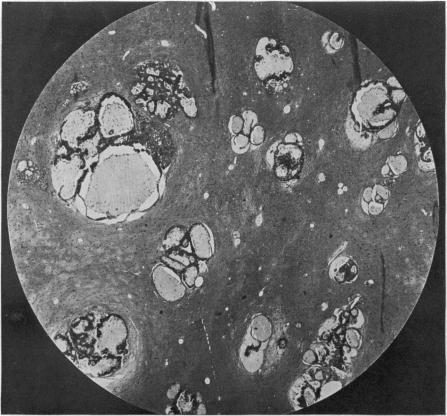

CONCERNING INTRACRANIAL MALIGNANT METASTASES: THEIR FREQUENCY AND THE VALUE OF SURGERY IN THEIR TREATMENT.

Ann Surg. 1926 Nov;84(5):635-46.